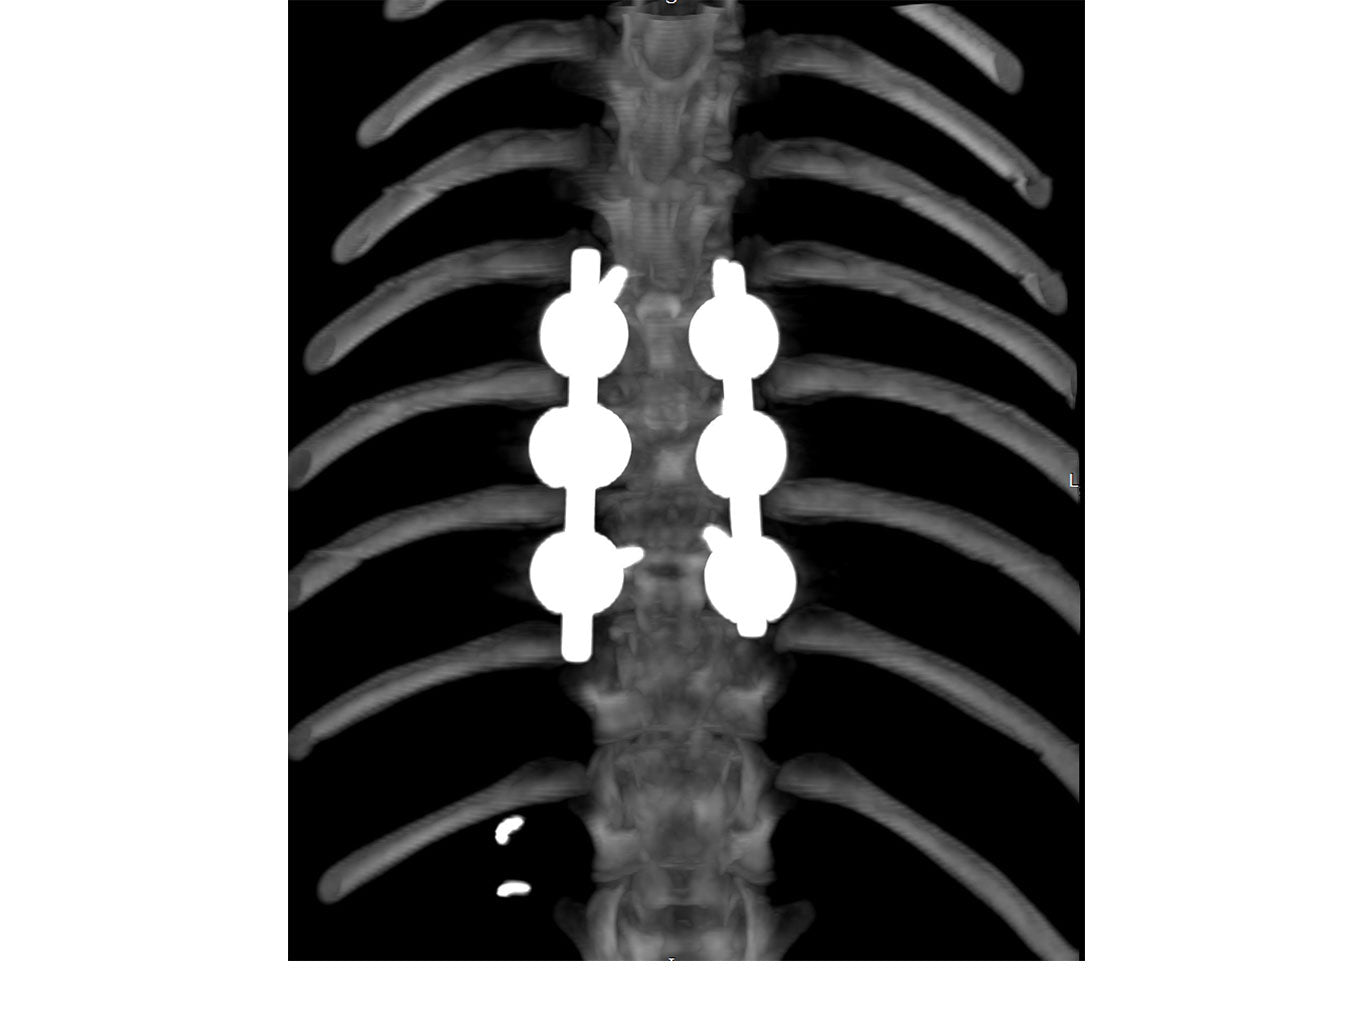

• Polyaxial screws with ball design with multiple degrees of freedom to increase screw placement options and allows placement in many different fashions

• System consists of screws, caps and rods

// User Cases

Highlighting the cases of these products in real-life situations is vital to demonstrating their success. Below are cases studies of long-term follow up surgeries.